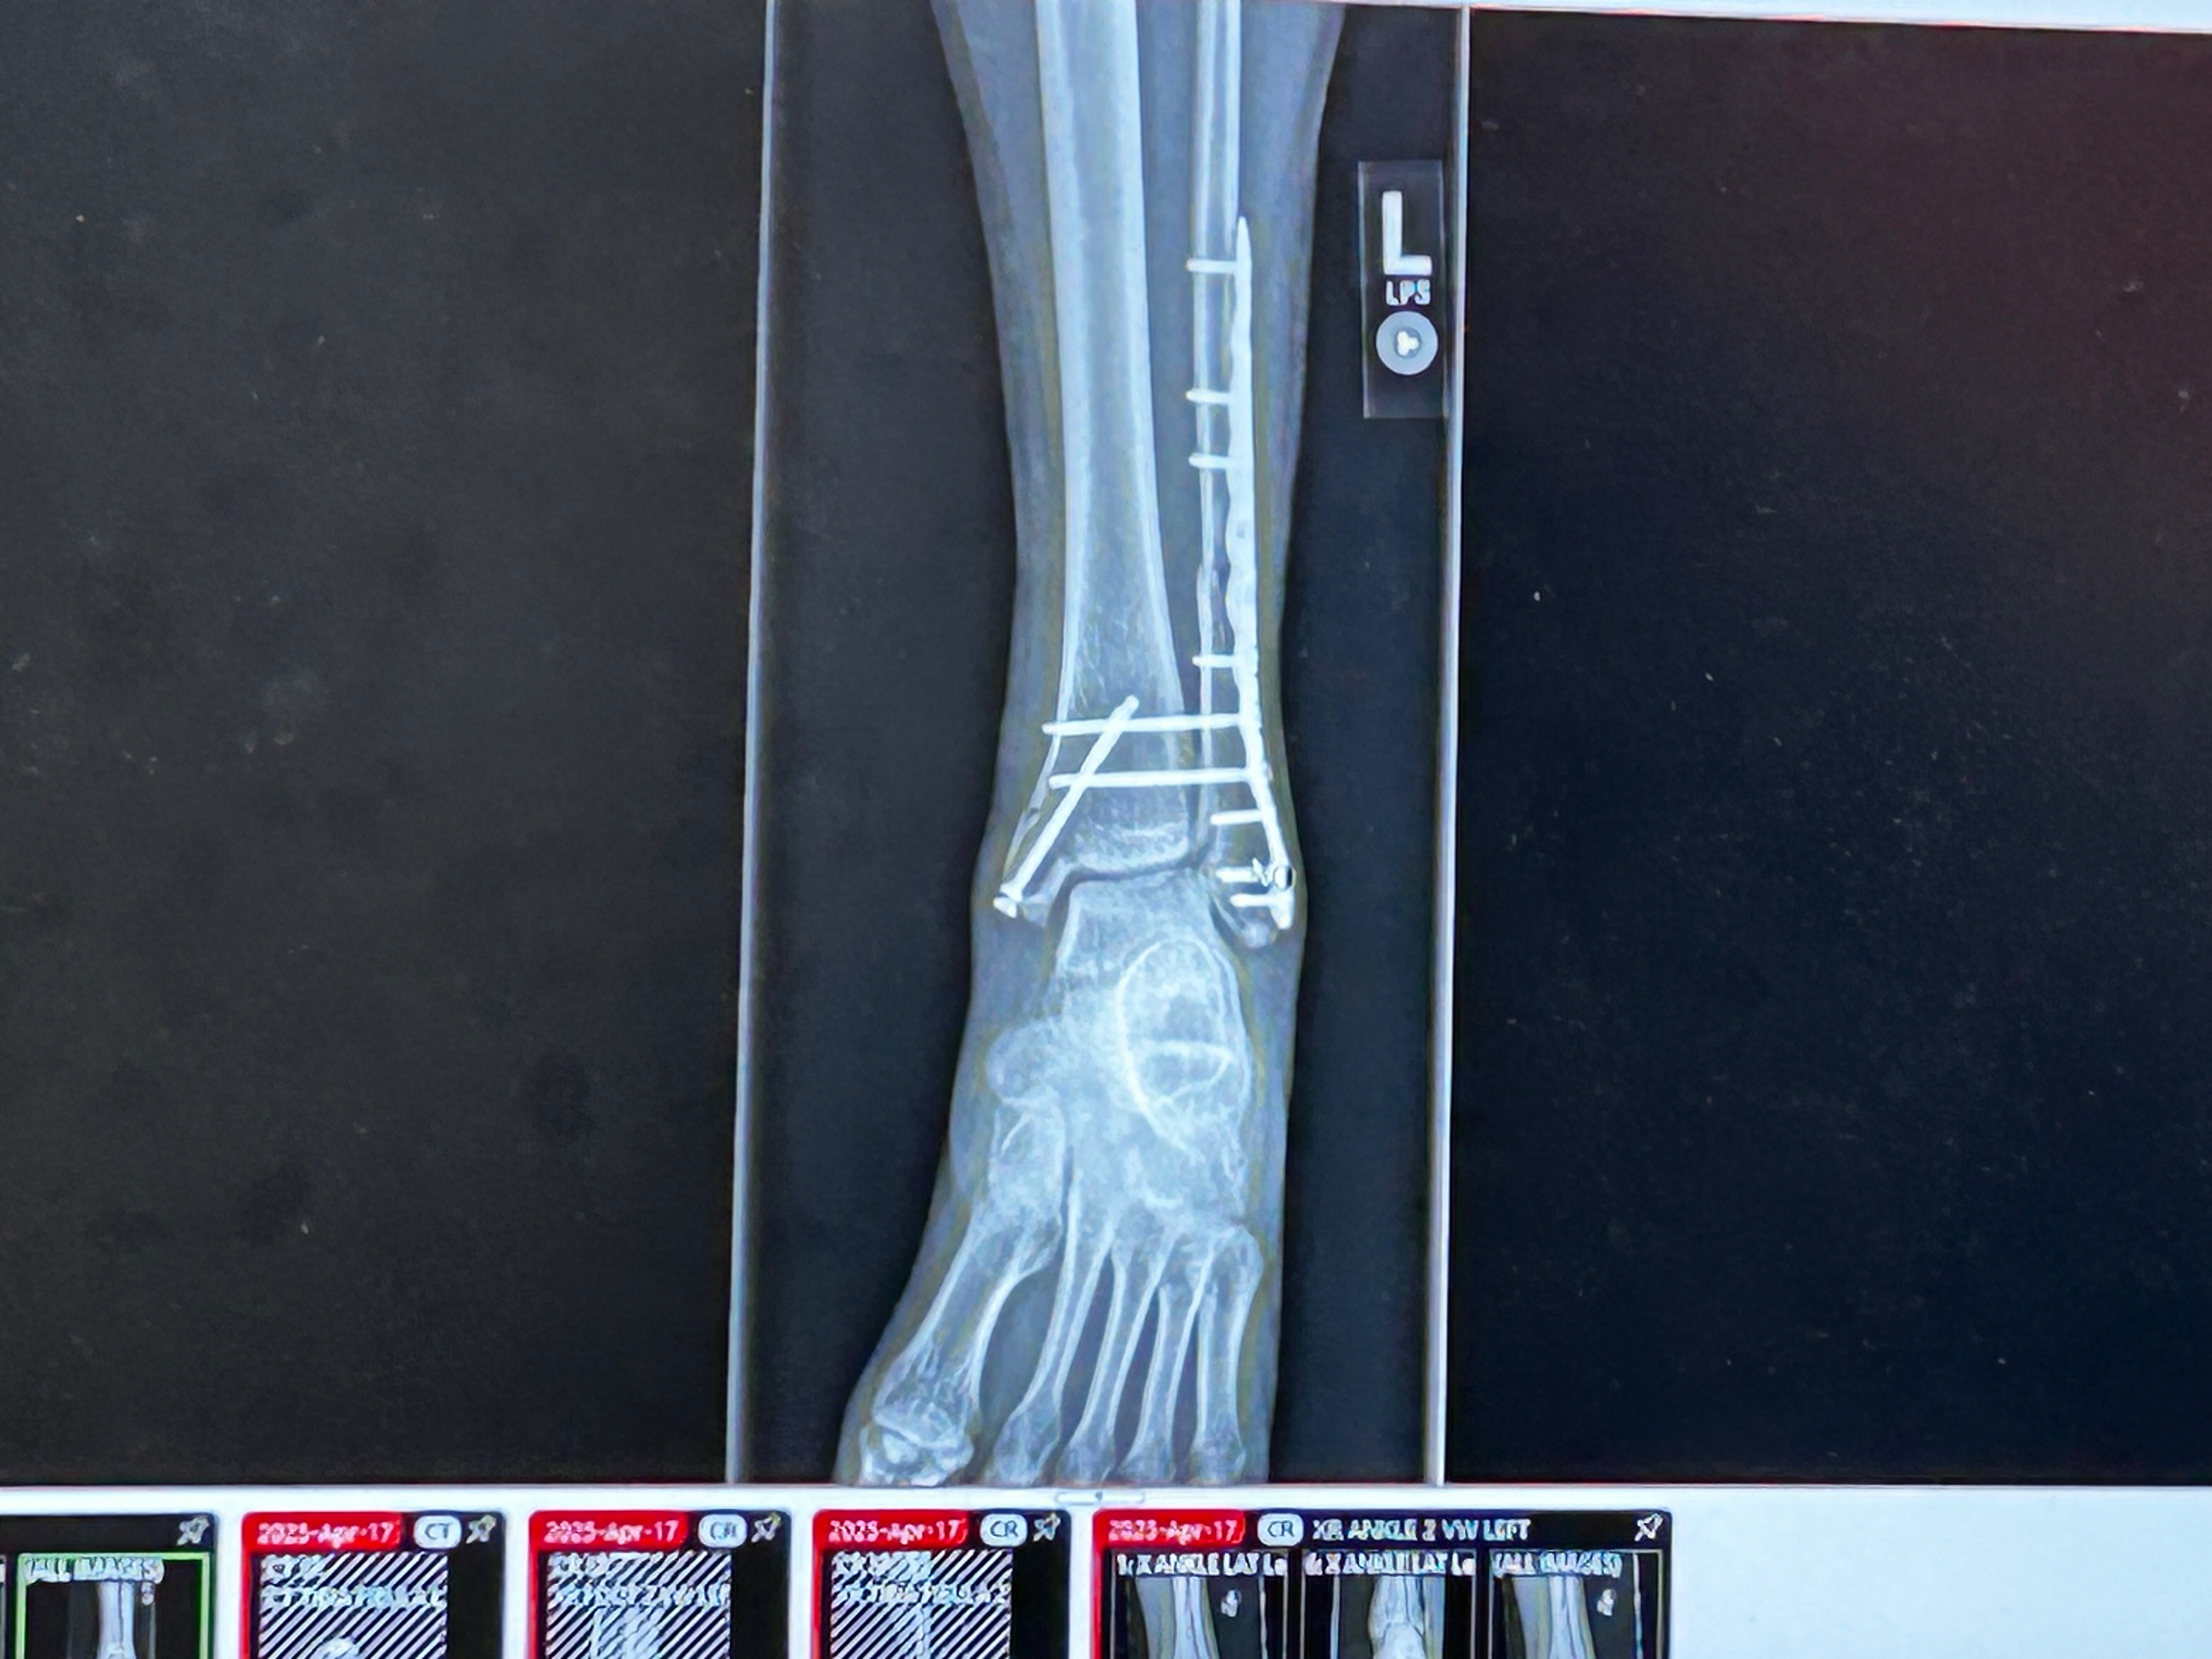

I'm reaching out on behalf of my amazing brother, Rj, who recently suffered a serious accident. He broke his leg/ankle in three places, a complex break that required surgery and will take months of recovery and physical therapy before he can walk again, let alone return to work.